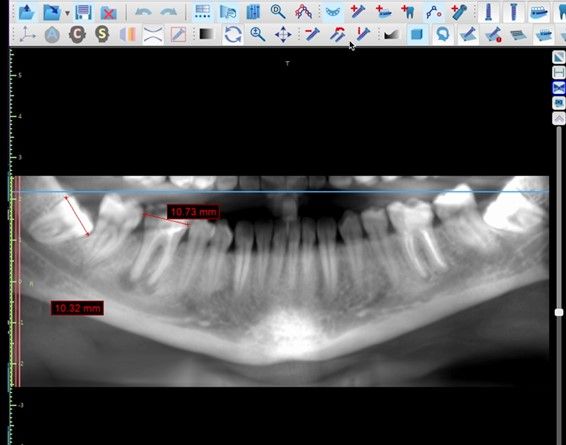

El sitio receptor debe garantizar la adaptación del diente donante, se realizará un diagnóstico mediante planificación con CBCT que permita segmentar virtualmente el diente donante y llevarlo digitalmente al sitio receptor3.

La confección de la réplica 3D del diente se ha de realizar con material biocompatible y esterilizable mediante radiación gamma y beta. La ventaja del modelo estereolitográfico es minimizar el tiempo extraoral del diente donante, el daño al ligamento periodontal, así como poder remodelar el alveolo receptor sin usar el diente donante5,13,14.

El autotrasplante dental es una opción terapéutica para aquellos casos en la que una pérdida dentaria es reemplazada por un diente donante del mismo paciente. Este autotransplante colocado en el alveolo puede ser inmediato o diferido. Suele estar indicado en paciente joven, siendo más frecuente el autotransplante de cordal a primer o segundo molar, y el de premolar a incisivo. El diente donante debe reunir unos criterios clínicos que aumenten el éxito de la técnica, basados en la morfología, el estadio de desarrollo radicular y la salud periodontal. La planificación se llevará a cabo con un CBCT y simulación virtual que genere un prototipo réplica en 3D; esto permite evaluar las dimensiones del diente donante para su correcta colocación en el alveolo receptor.

Se reporta el caso de un autotrasplante del tercer molar inferior derecho al alveolo postextracción de un primer molar inferior, en una paciente de 22 años de edad. Actualmente, el autotransplante se considera una opción de tratamiento si se siguen los criterios de selección del caso adecuados, y se realiza una técnica quirúrgica protocolizada. El diagnóstico planificado mediante CBCT, la simulación virtual y la confección de una réplica en 3D optimiza la técnica de forma segura, predecible con tiempos de cirugía menores.

González-Quintanilla D, Zamorano JP, Mella E et al. Dental autotransplantation using virtual simulation and a prototype 3D printing model. Int J Odontostomat. 2021;15:271-277.